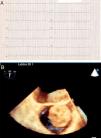

Three ways for the same symptom: Syncope caused by myxoma

Tres mecanismos para un síntoma: síncope por mixoma

Figuras (3)